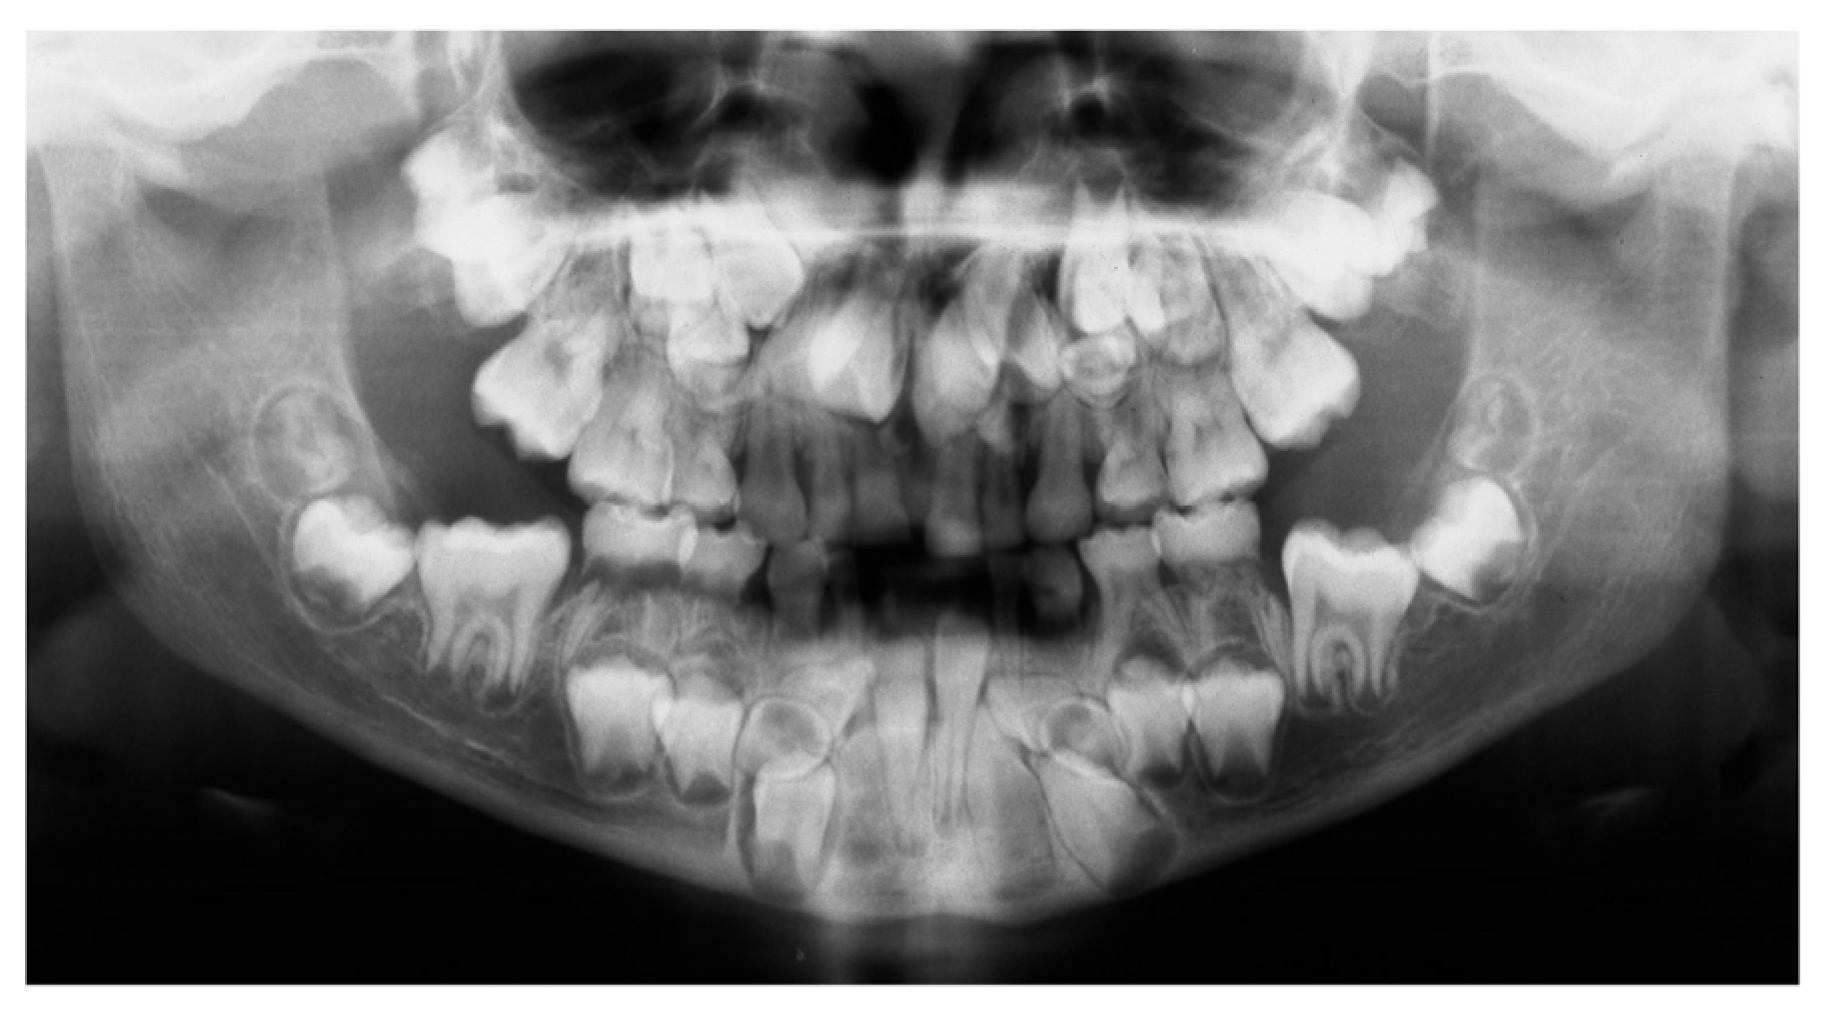

| Abnormal height | Hyperdontia |

| Open fontanelles | Supernumerary tooth germs |

| Bone-related problems | Wide spacing in the lower incisor area |

| Clavicular hypoplasia | Parallel-sided ascending rami |

| Congenital hip luxation | Altered eruption pattern |

| Joint hypermobility | Gingival cysts |